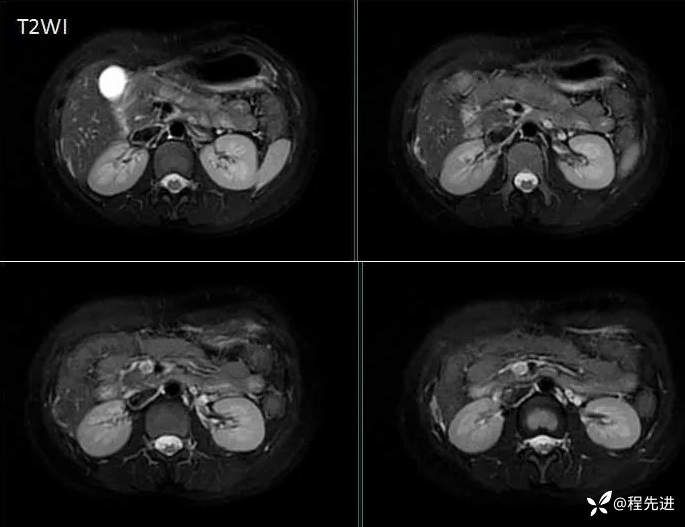

MRI检查: